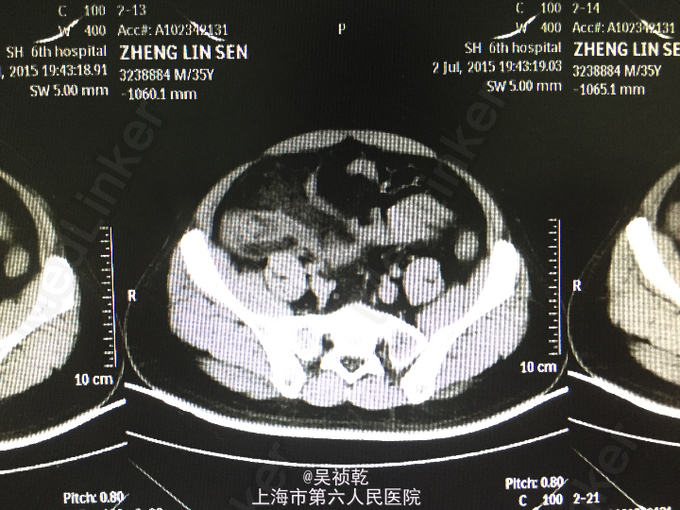

患者男性,35岁。因“右下腹疼痛1天,伴恶心、呕吐”入院。患者1个月前无明显诱因下脐周疼痛,后转移至右下腹,疼痛固定。无恶心呕吐,无头晕乏力。于外院拟尿路感染治疗,补液消炎1周后症状缓解。昨日下午,右下腹疼痛加剧,伴发热,体温约38.2摄氏度,有恶心,呕吐症状。故来我院治疗,完善各项检查,查腹部CT;阑尾形态增粗伴阑尾壁肿胀,回盲部及阑尾周围可见大量渗出,前列腺密度均匀,未见明显增大,两侧精囊未见明显异常,膀胱充盈可,盆腔未见明显肿大淋巴结,盆腔未见明显积液,。为进一步治疗收住入院。患者自起病以来,精神可,胃纳差,大便如常,小便如常,体重未见明显下降,睡眠一般。

查体:腹部平坦,无胃肠型。腹壁柔软,有压痛,位于右下腹,伴反跳痛,无腹部包块,振水音阴性,未触及肝;未触及脾 ,无移动性浊音,肝区无叩痛。肠鸣音正常。结肠充气试验:阴性;腰大肌试验:阴性;闭孔内肌试验:阴性。 辅查:2015-7-3 生化检验报告:血清钠(干式) 136 mmol/L ↓,总蛋白(干式) 60 g/L ↓,白蛋白(干式) 32 g/L ↓,谷草转氨酶(干式) 14 U/L ↓,总胆红素(干式) 62 μmol/L ↑。 血常规检验报告:白细胞 14.3 X10^9/L ↑,红细胞 5.18 X10^12/L ,淋巴细胞百分比 9.5 % ↓,嗜酸性细胞百分比 0.1 % ↓,中性细胞百分比 84.8 % ↑,嗜酸性细胞绝对值 0.01 X10^9L ↓,单核细胞绝对值 0.8 X10^9L ↑,中性细胞绝对值 12.1 X10^9L 腹部CT:阑尾形态增粗伴阑尾壁肿胀,回盲部及阑尾周围可见大量渗出,前列腺密度均匀,未见明显增大,两侧精囊未见明显异常,膀胱充盈可,盆腔未见明显肿大淋巴结,盆腔未见明显积液,。

患者入院诊断:急性阑尾炎,入院后本准备急诊手术,但患者家属坚决要求保守治疗,故予保守治疗,但患者第二天腹痛症状及体征没有缓解,且出现高热伴巩膜轻度黄染,诊断为:急性阑尾炎伴周围大量渗出,同时合并门静脉炎,故于第二天行阑尾切除术,术中见腹腔内渗出液100ml(脓液),有臭味。阑尾长10cm,粗直径1cm,阑尾有坏疽,多处穿孔,根部坏疽穿孔,阑尾与小肠粘连,阑尾为回肠后位。分离粘连,结扎处理阑尾系膜,于阑尾根部切下阑尾,阑尾根部之回盲部行间断缝合修补 残端闭合方式 。探查回盲部及升结肠根部10cm,回肠末端30cm,未见其他病变。 于回盲部修补处放置双套管一根,盆腔放置负吸球一根,清点纱布及器械无误,逐层关闭切口,切口留置皮片引流。术后诊断:急性阑尾炎伴坏疽穿孔,术后予抗炎等对症支持治疗,术后仍有反复发热,术后3天体温消失,术后一周恢复出院。